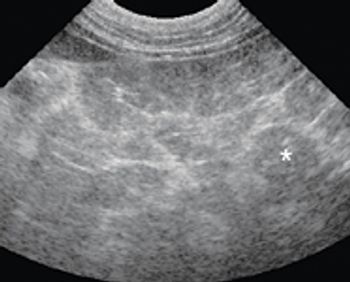

Chronic renal disease is one of the most common ultra-sonographic findings in older cats. If you're doing ultrasounds on cats, you're sure to see signs of chronic renal changes daily.